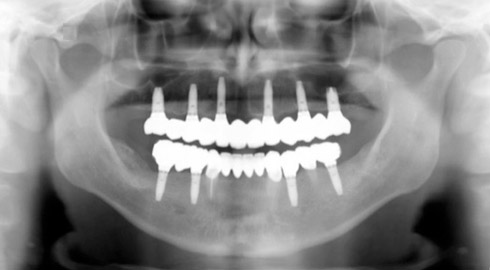

Exemple d’une réhabilitation complète implantaire

Situation clinique terminée